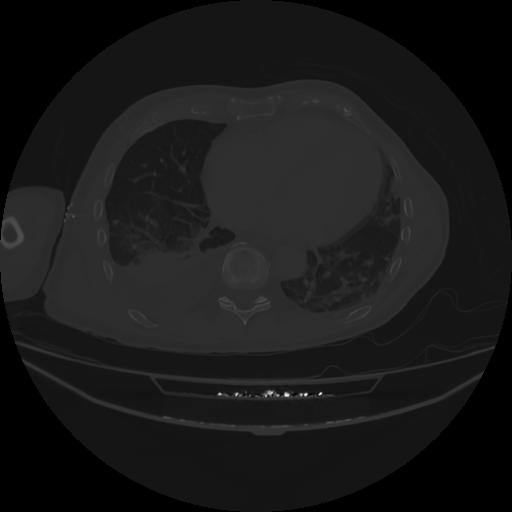

5 CUERPO,CE,Vol,1.0,CUERPO,,